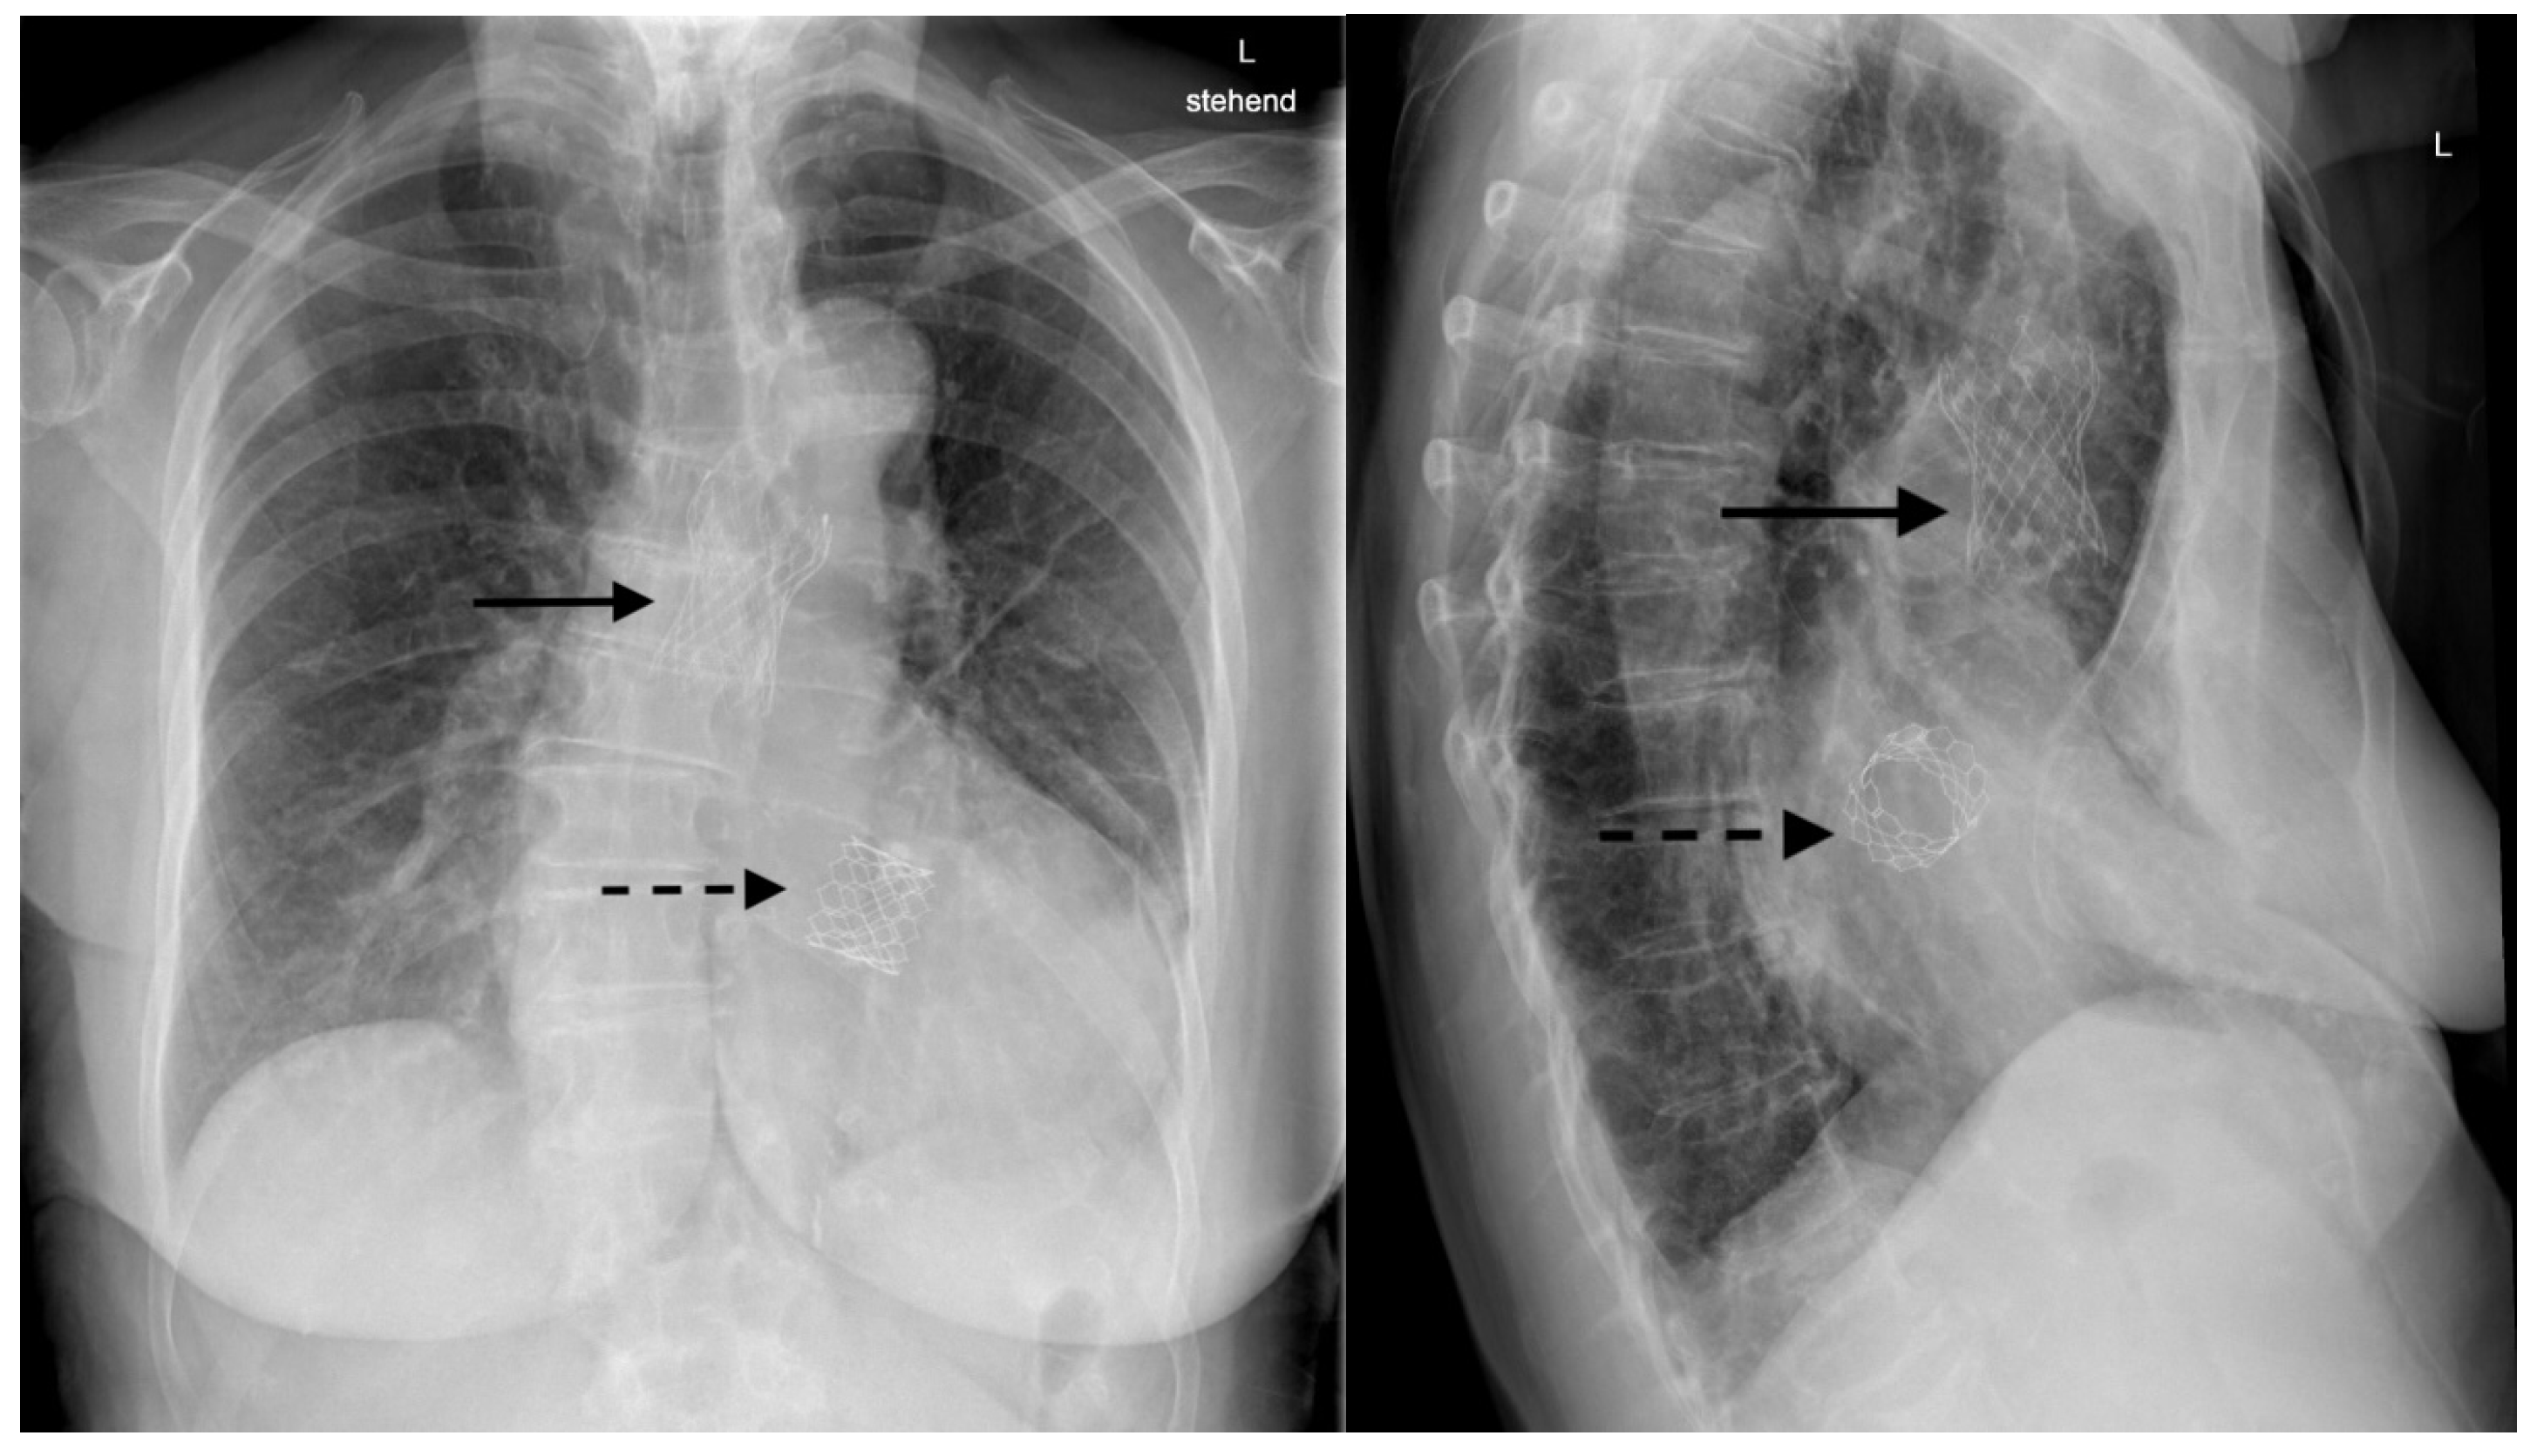

After recovery from the TAVI in the presence of clinical signs of heart failure, a chest X-ray and a repeat transthoracic echocardiography were performed to assess the position of the grafts (Figure 2).

Figure 2. Double transcatheter aortic valve implantation. The embolized prosthesis is in the ascending aorta (dashed arrow), and the second aortic valve prosthesis is in the correct position (arrow).